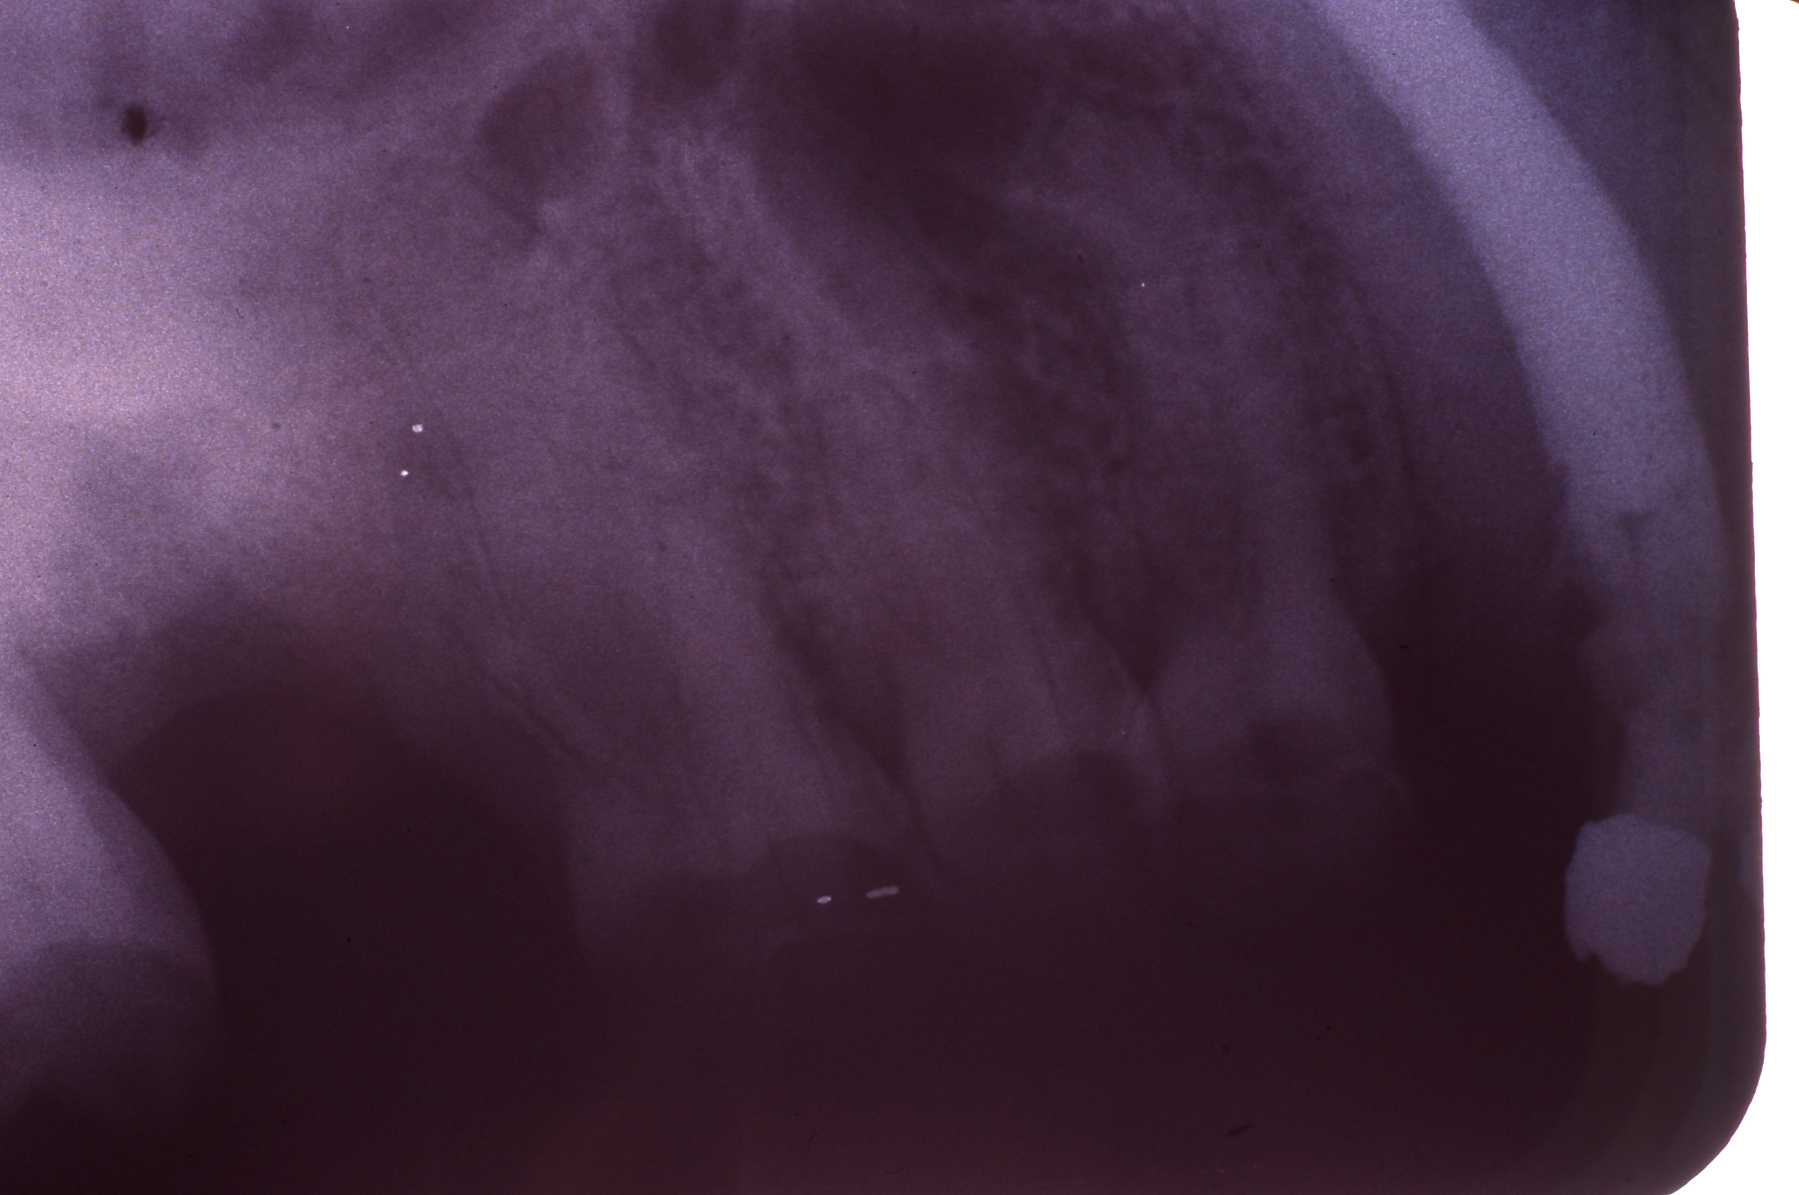

Exam: Fractured maxillary left canine (no. 15 or 207), extraoral chronic drainage tract adjacent to nostril and oral antral fistula where maxillary second molar had been extracted by veterinarian

Fractured canine with exposed pulp cavity

Radiograph of canine

Radiograph of fistula

Radiograph of bone repair three (?) months post op